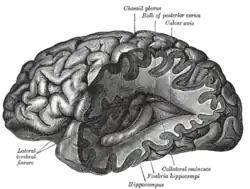

Stereotactic guided insertion of DBS electrodes in neurosurgery | |